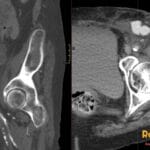

- Radiology Cases: Images with a to-the-point discussion highlighting the specific diagnostic criteria.

- Radiology Case of the Day Collection: Aunt-Minnie Board Cases for Rapid Review.

- Radiology Spotters: 700+ spot / “Aunt-Minnie” cases divided into sets of 10 each!